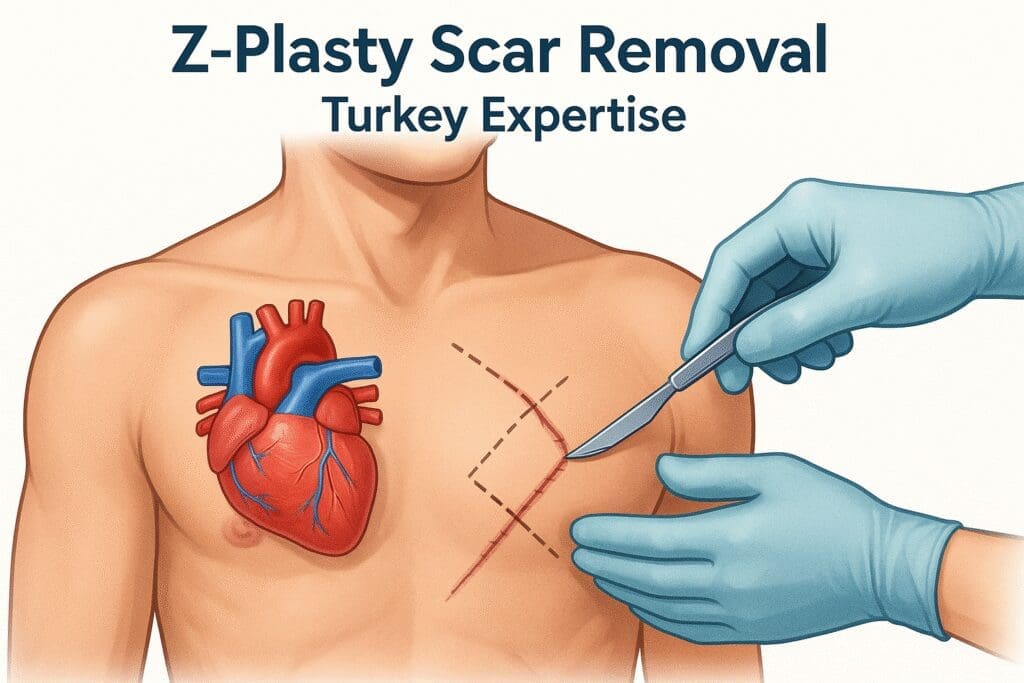

مقالات طبية من مساهمات الأطباء